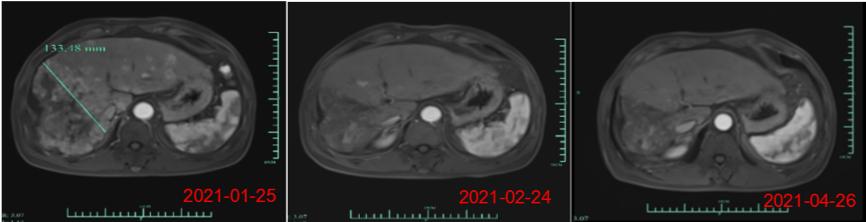

美国东部时间2021年6月4日 , 原启生物联合浙江大学附属丽水市中心医院和上海长征医院在2021年美国临床肿瘤学会(ASCO)年会上首次公布其评估靶向GPC3的CAR-T药物(Ori-CAR-001)治疗复发/难治性肝细胞癌(hepatocellular carcinoma , HCC)的最新临床研究数据(Abstract ID: 4095) 。 该研究的初步数据显示 , Ori-CAR-001在GPC3阳性复发/难治性患者中表现出良好安全性和有效性 。文章插图

杨焕凤表示 , 近期公司在美国临床肿瘤学会 (ASCO)发表了核心产品Ori-CAR-001在治疗难治复发型肝细胞癌的探索性临床研究数据 , 截至三月份 , 在9例可评估数据中 , 有4例获得PR(部分缓解) , 截止到目前 , 受试者007的缓解周期已超过是9个月 , 还有一例受试者012的PR缓解周期已达5个月 , 其肿瘤缩减的幅度接近93% 。 此外 , 最近的一个新的爬坡剂量的首个患者也获得了PR(自ASCO数据发布后 , 又新增了一位部分缓解的病人) 。 目前 , 这些病患目前仍在持续随访中 。 “在晚期实体肿瘤治疗中 , 这个缓解时间还是相当长的 , 肿瘤减小的幅度也是非常惊人的 , 这个结果令团队很受鼓舞 , 我们期待在进一步的产品开发和临床研究过程中 , 获得更好的数据 。 ”